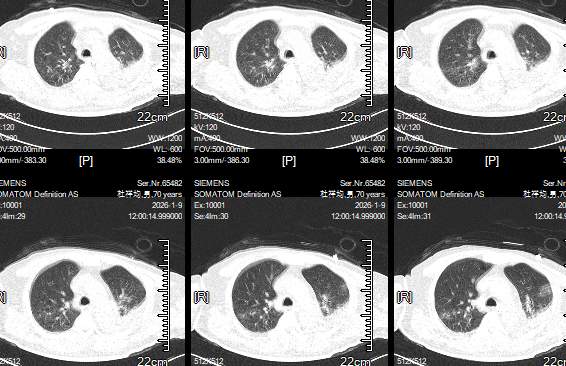

术后两周复查胸部CT:肺部情况好转